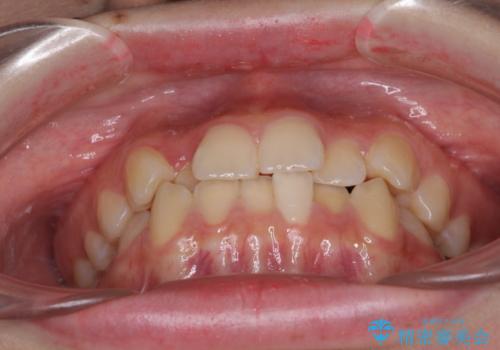

前歯のクロスバイト メタル装置での矯正治療

- 前歯のクロスバイトを気にして来院された患者様です。

前歯の叢生を解消するスペースを獲得するために上顎左右の親知らずを抜歯し、メタルブラケットにて矯正治療を行うこととしました。